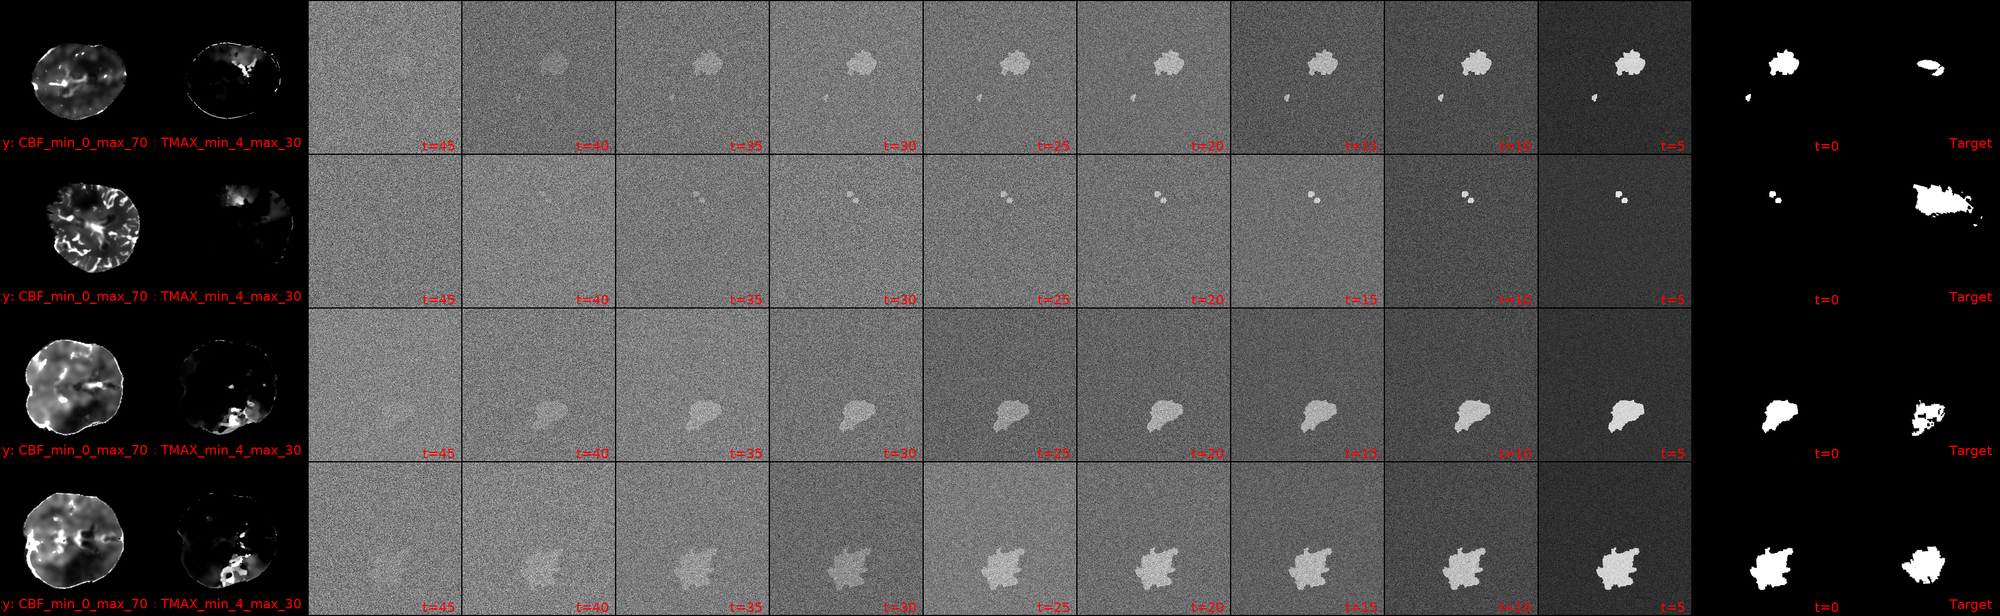

I dont know whether you can see it, but I can. This is a snapshot from one of my current crop of diffusion models! First out the gate, lets ground our expectations: the Dice scores are still s*it, with the maximum -current- score being 6.5%.

That being said, I'm still going to shamelessly showcase a few cherry picked samples that show how we actually now have clean blacks at the end of our diffusion inference! We also have segmentation masks that (to some degree) match the actual lesions in shape/location.